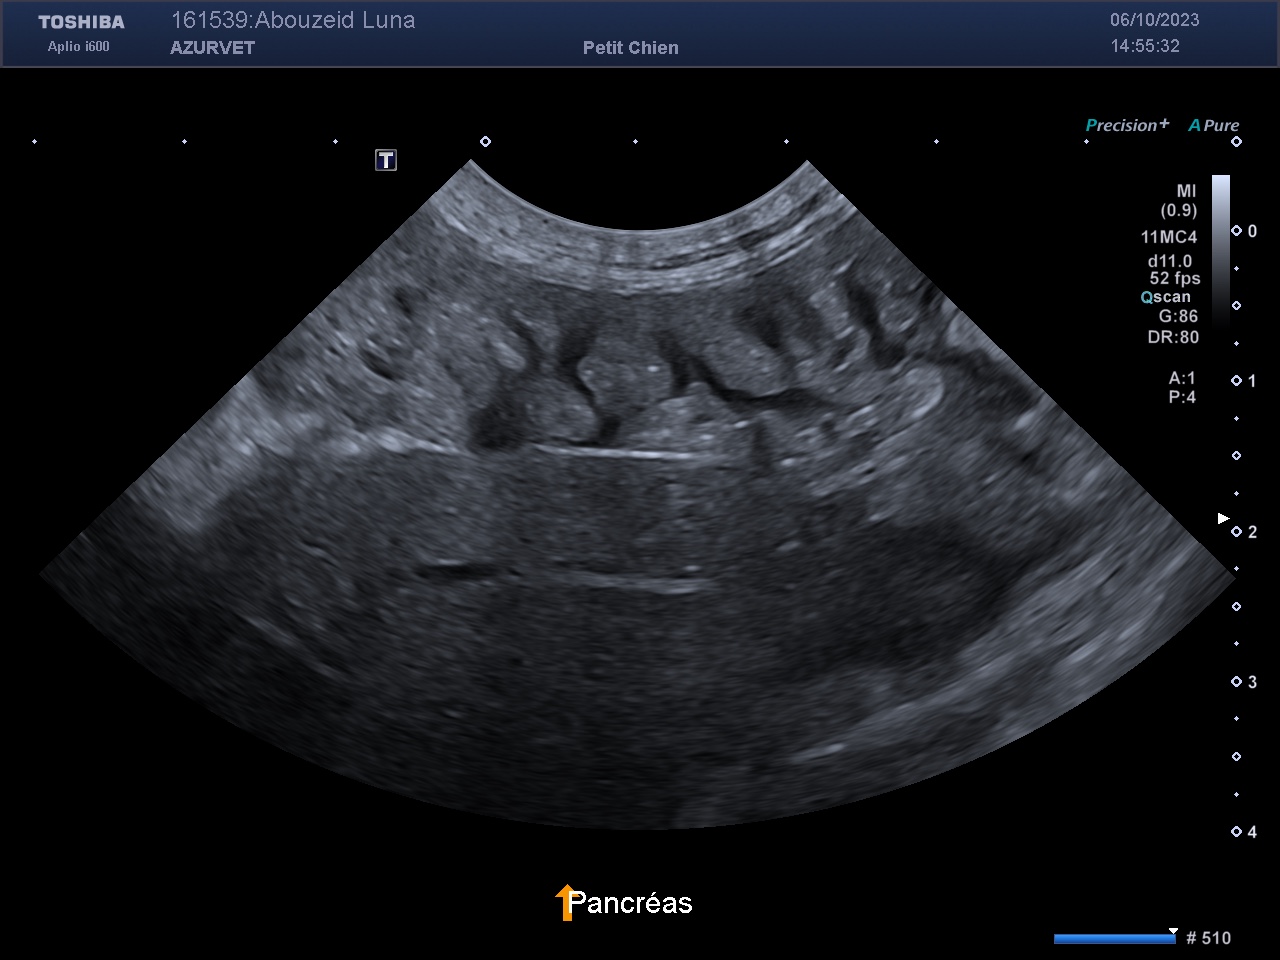

2) Un épaississement avec aspect zébré du pancréas (travées hypoéchogènes lunéaires) lié à un oedème (secondaire à l'hypoalbuminémie) : figure 3 ci dessous.

Figure 3 : échographie du pancréas d'un Cairn de 9 ans souffrant de lymphiectasie avec épaississement et aspect zébré du pancréas.